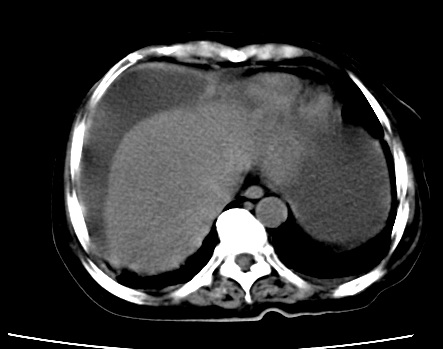

既往5年前卵巢癌行子宫及附件切除,右乳癌术后一年,考虑腹膜转移?

大量腹水,考虑腹膜转移。肝脏低密度灶。1囊肿,2转移。

1)结合病史,考虑腹膜及网膜转移瘤。2)肝脏多发性低密度灶,不排除转移瘤。3)大量腹水。

考虑卵巢癌行子宫术后复发,并肝、腹腔 、大网膜转移可能性大。

大量腹水。